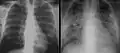

يمكن تأكيد التشخيص من خلال المظهر الوصفي على صورة الصدر البسيطة بأشعة إكس والضغط الجزئي للأكسجين في الدم الشرياني الذي يكون أخفض من المتوقع تبعًا للأعراض بشكل غريب. يعتبر المسح بالغاليوم 67 مفيدًا في التشخيص. يبدي المسح موجودات غير طبيعية في 90% من الحالات وعادة ما يكون إيجابيًا قبل أن تصبح صورة الصدر البسيطة بأشعة إكس غير طبيعية. تظهر صورة الصدر البسيطة عادة ارتشاحات رئوية منتشرة. قد يظهر التصوير المقطعي المحوسب كيسات رئوية (لا يجب الخلط بينها وبين الأشكال الكيسية للعامل الممرض).